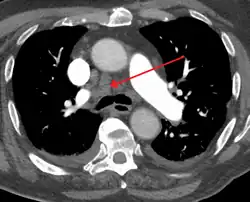

Widened mediastinum

Other namesMediastinal widening

Widened mediastinum in a patient with achalasia

Widened mediastinum/mediastinal widening is where the mediastinum has a width greater than 6 cm on an upright PA chest X-ray or 8 cm on supine AP chest film.[11]

A widened mediastinum can be indicative of several pathologies:[12][13]